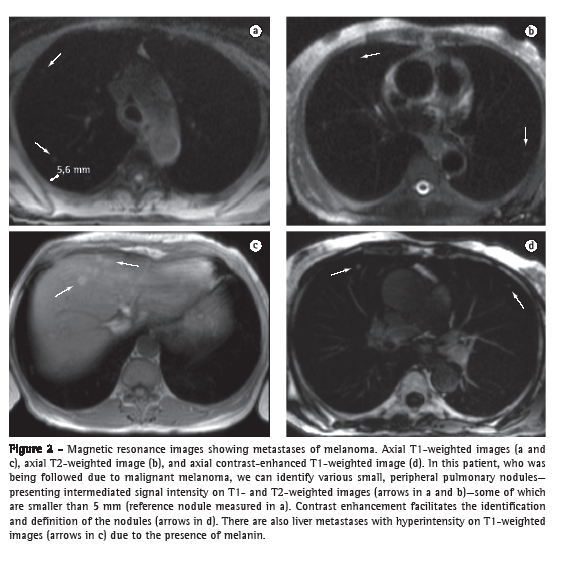

The accuracy of MRI in detecting nodules larger than 4-5 mm is greater than is that of routine X-ray, and the specificity and sensitivity of MRI can be as high as 93% when compared with those of multidetector CT.(18) The sensitivity of MRI is directly related to the size of the nodule. Sensitivity is lower for nodules smaller than 5 mm, whereas it is nearly 100% for the detection of nodules ≥ 10 mm (Figure 2). Therefore, MRI of the lung (principally with the HASTE and 3D GE sequences) should be used as a complementary test in studies of the heart and chest wall, as well as in those of mediastinal lesions. It can also be used as an alternative to CT in screening for lung metastases. The principal limitations of MRI in the study of focal pulmonary lesions include its limited ability to characterize calcified lesions and to detect lymphangitic carcinomatosis.(18-20)

Dynamic contrast-enhanced MRI can be performed to characterize solitary pulmonary nodules and is useful in differentiating between benign and malignant lesions. The specificity of MRI in such cases is greater than is that of dynamic CT, and its accuracy is similar to that of positron emission tomography (PET). The sensitivity of the combination between morphological evaluation and evaluation of perfusion for the differentiation of solitary nodules can be as high as 100%, whereas the specificity is only 79%.(21,22) Malignant nodules are delineated by predominantly nodular enhancement that is rapid and intense and is detected in the early (arterial) phase, with higher peak enhancement and, subsequently, contrast washout. Active inflammatory nodules can present early enhancement; however, enhancement persists or progresses in later phases, whereas washout is considered a highly specific sign of malignancy. Benign nodules, including hamartomas and granulomas, show predominantly peripheral enhancement that is less intense and slower, whereas cysts show no enhancement.(22,23) Other morphological characteristics of benign nodules, such as the typical appearance of hamartomas, with high T2 signal intensity, foci of fat, and internal septations or clefts, can be accurately identified by MRI.(24)